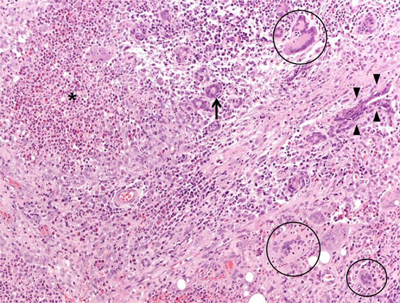

Figure 1

Microphotograph (magnification: 40X) showing a granulomatous mastitis. Mammary parenchyma is characterized by the presence of dense necrotic foci (asterisk), giant multinucleated cells (circles), and normal breast ducts in transversal (arrow) and longitudinal section (arrowheads), trapped by neutrophilic-eosinophilic infiltrate.